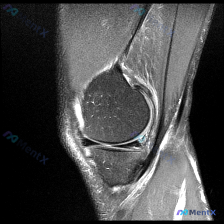

刚看到这个膝关节MRI读片的病例,有点典型,整理出来和大家分享一下思路。 病例基础信息 这是一份膝关节矢状位MRI影像,序列为T2WI或PDWI-FS,对软组织、水肿、韧带病变显示清晰。 影像学核心发现 1. 骨骼与关节软骨:髌骨后方关节软骨面不平整,髌骨软骨下骨可见片状高信号影,提示骨髓水肿或软骨...

刚看到一份膝关节MRI单矢状位切面的读片需求,核心问题是观察半月板异常,我整理了完整的分析思路分享给大家。 一、病例基本影像信息 这是一张膝关节矢状位MRI影像,根据信号特征判断:不符合典型T1加权像(骨髓信号偏低,关节软骨、积液呈高信号),更符合质子密度加权像(PDWI)或T2加权像,这类序列对半...

今天遇到一个很有代表性的情况:用户提供了一张膝关节矢状位MRI,主诉提示「半月板异常」,但我们阅片后发现结果和预期完全不一样,整理出来给大家讨论。 基本影像信息 这是一张膝关节矢状位质子密度或T2加权MRI,图像清晰度良好,信噪比适中,没有明显运动伪影,解剖结构显示清晰,层面大致位于膝关节中部区域。...

刚整理了一份膝关节MRI读片病例,分享一下完整分析思路。 病例影像基本信息 这是一张膝关节MRI矢状位图像,用户提问是否存在半月板异常,我们来一步步分析: 影像基础评估结果 1. 骨骼与关节: 股骨远端、胫骨近端皮质连续,无明显骨折,无明显骨髓水肿、软骨下囊肿,关节间隙和对合关系基本正常 2. 关节...

病例读片分享:临床怀疑半月板异常,MRI却只看到髌周病变 基本影像信息 提供的影像为膝盖MRI-T2序列矢状位,切面位于膝关节前部髌股关节区域,图像存在一定截断伪影,未显示后交叉韧带及大部分后侧软组织结构。 影像核心发现 整理一下客观观察到的异常: 1. 髌前皮下软组织水肿:髌骨前方及皮下组织层可见...